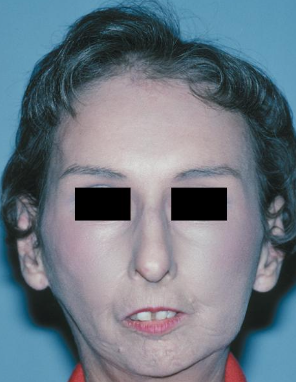

Lupus cheilitis in Systemic Lupus Erythematosus

Butterfly rash in

Systemic Lupus Erythematosus

What are the clinical features of scleroderma?

Raynaud phenomenon (not specific for scleroderma)

Mask-like face, loss of ala of nose